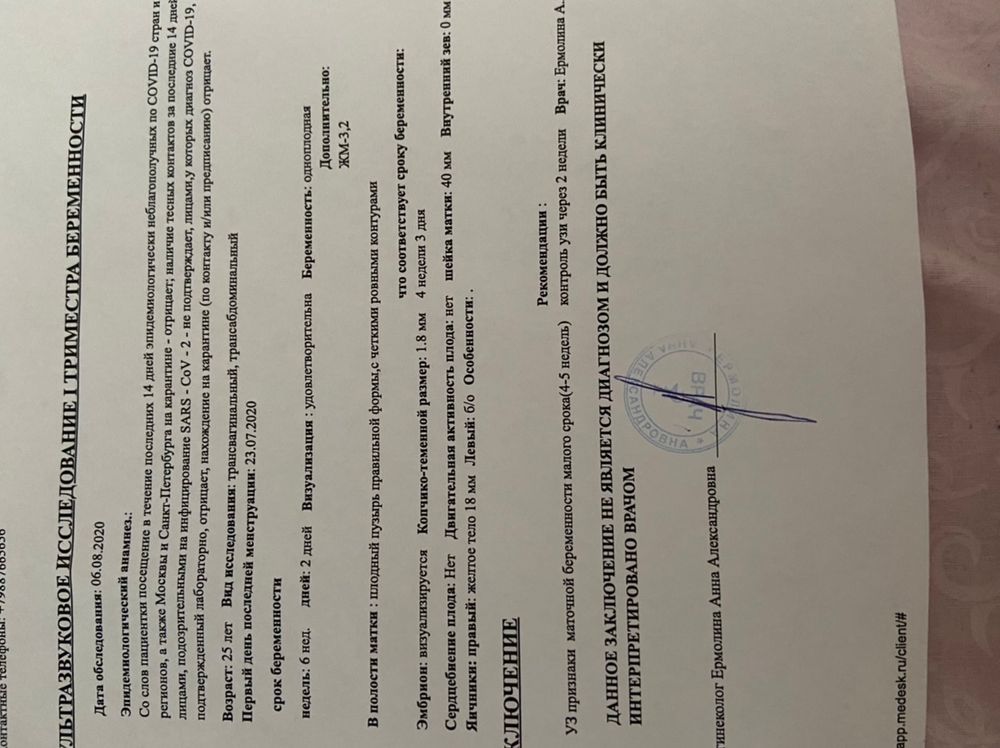

Была 8 дней назад на узи, ктр был 1,8. Сб ещё не было, но увидели пульсацию слегка. Сегодня сходила к другому специалисту, тк к той не было записи долго. Узист сказал все прекрасно, кроме расширения моих вен. Но когда я вышла из кабинета увидела что ни ктр, ни чсс не указано, вернулась, он сказал что чсс забыл дописать(дописал 158? Это норма? По таблицам много), а ктр на таком сроке не смотрят, смотрят кровоток и жм 🤷🏽♀️🤷🏽♀️🤷🏽♀️Но как тогда он ставил срок 6+3 без ктр, сказал программа выставила и это точный срок. узи за сегодня и фото за сегодня, так же и прошлое узи вставлю для ясности. Посмотрите пожалуйста, иначе я с ума сойду до скрининга 🤦🏽♀️🤦🏽♀️🤦🏽♀️ Вообще не планировала больше на узи до скрининга идти, но теперь ещё непонятнее чем было